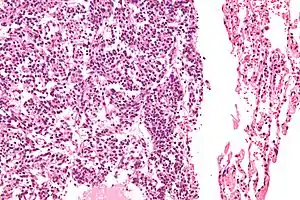

| Micrograph of a typical pulmonary carcinoid tumour. | |

The definitive diagnosis is rendered by a microscopic examination, after excision. Typical carcinoids have cells with stippled chromatin and a moderate quantity of cytoplasm. They typically have few mitoses and lack necrosis. By definition, they are greater than 4 mm in largest dimension; smaller lesions are referred to as pulmonary carcinoid tumourlets.